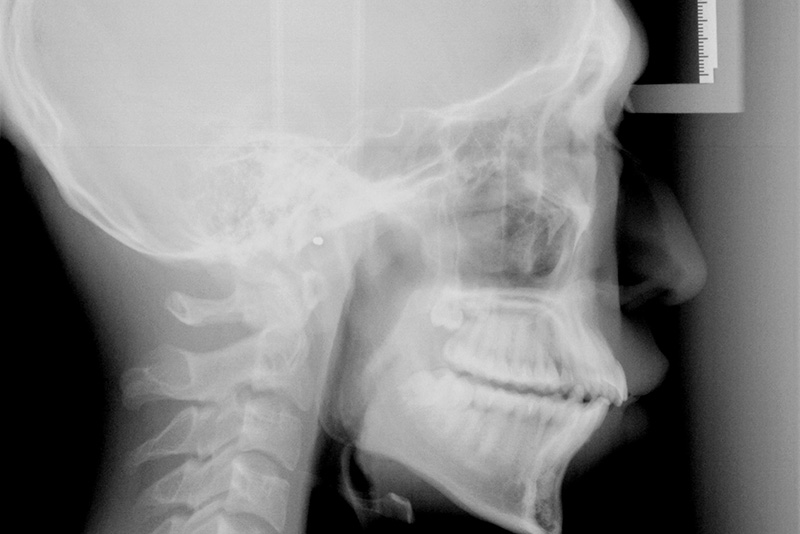

セファロ写真

また、矯正歯科治療の際にはセファロ写真(側方頭部X線規格写真)という特殊な撮影を行います。

セファロ写真は世界共通の撮影規格であり、この写真を用いて矯正治療の方針を決めていきます。

• X線管球の焦点―フィルム間距離は165cm

• 被写体―フィルム間距離は15cm